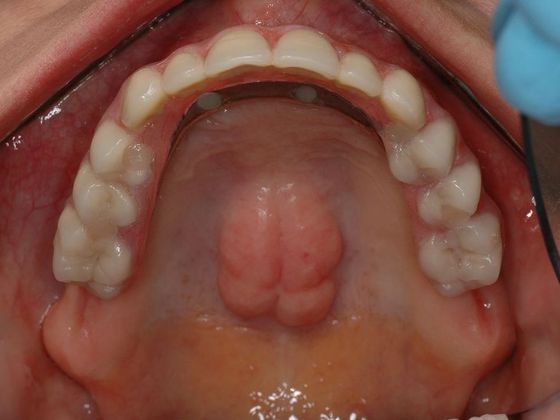

This fine lady was extremely unhappy with her partials and the bony bump on her palate prevented her from wearing anything that needed to be inserted and removed from her mouth. Removing this bony bump from the palate is a very invasive procedure so that was not an option. She was trying to hold on to the very last tooth to avoid wearing dentures.

Procedures : extractions, full mouth implants, All on 4 , Teeth in a day, full mouth reconstruction with implant bridges.